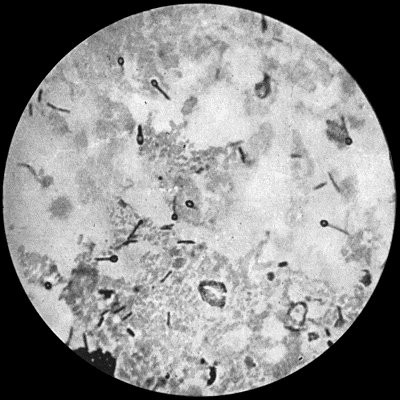

15 2.Staphylococcus aureus in Pus from case of Osteomyelitis

Fig. 2.—Staphylococcus aureus in Pus from case of Osteomyelitis. × 1000 diam. Gram's stain.

Staphylococcus Aureus.—This is the commonest organism found in localised inflammatory and suppurative conditions. It varies greatly in its virulence, and is found in such widely different conditions as skin pustules, boils, carbuncles, and some acute inflammations of bone. As seen by the microscope it occurs in grape-like clusters, fission of the individual cells taking place irregularly (Fig. 2). When grown in artificial media, the colonies assume an orange-yellow colour—hence the name aureus. It is of high vitality and resists more prolonged exposure to high temperatures than most non-sporing bacteria. It is capable of lying latent in the tissues for long periods, for example, in the marrow of long bones, and of again becoming active and causing a fresh outbreak of suppuration. This organism is widely distributed: it is found on the skin, in the mouth, and in other situations in the body, and as it is present in the dust of the air and on all objects upon which dust has settled, it is a continual source of infection unless means are taken to exclude it from wounds.